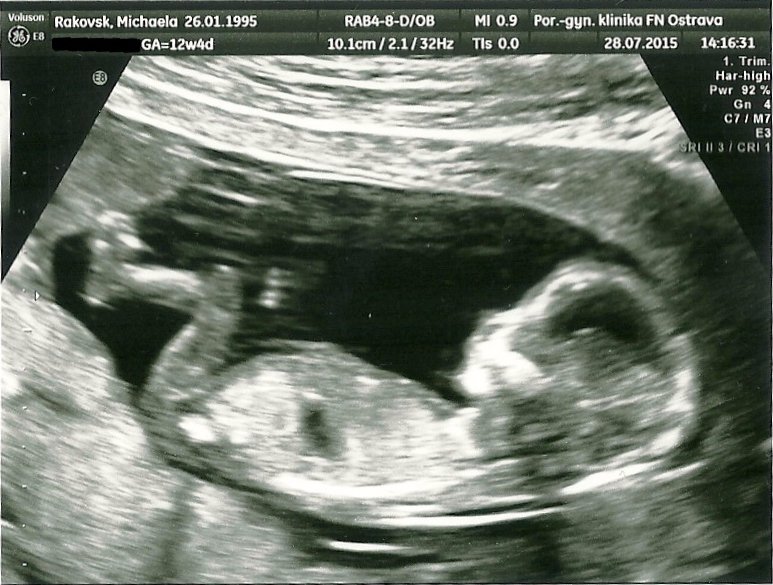

13tt :* A pindík se nám neukázal, takže zatím to vypadá na Laurinku :P Od zadečku k hlavičce měříme 7cm a máme kráááásnou fotečku <3